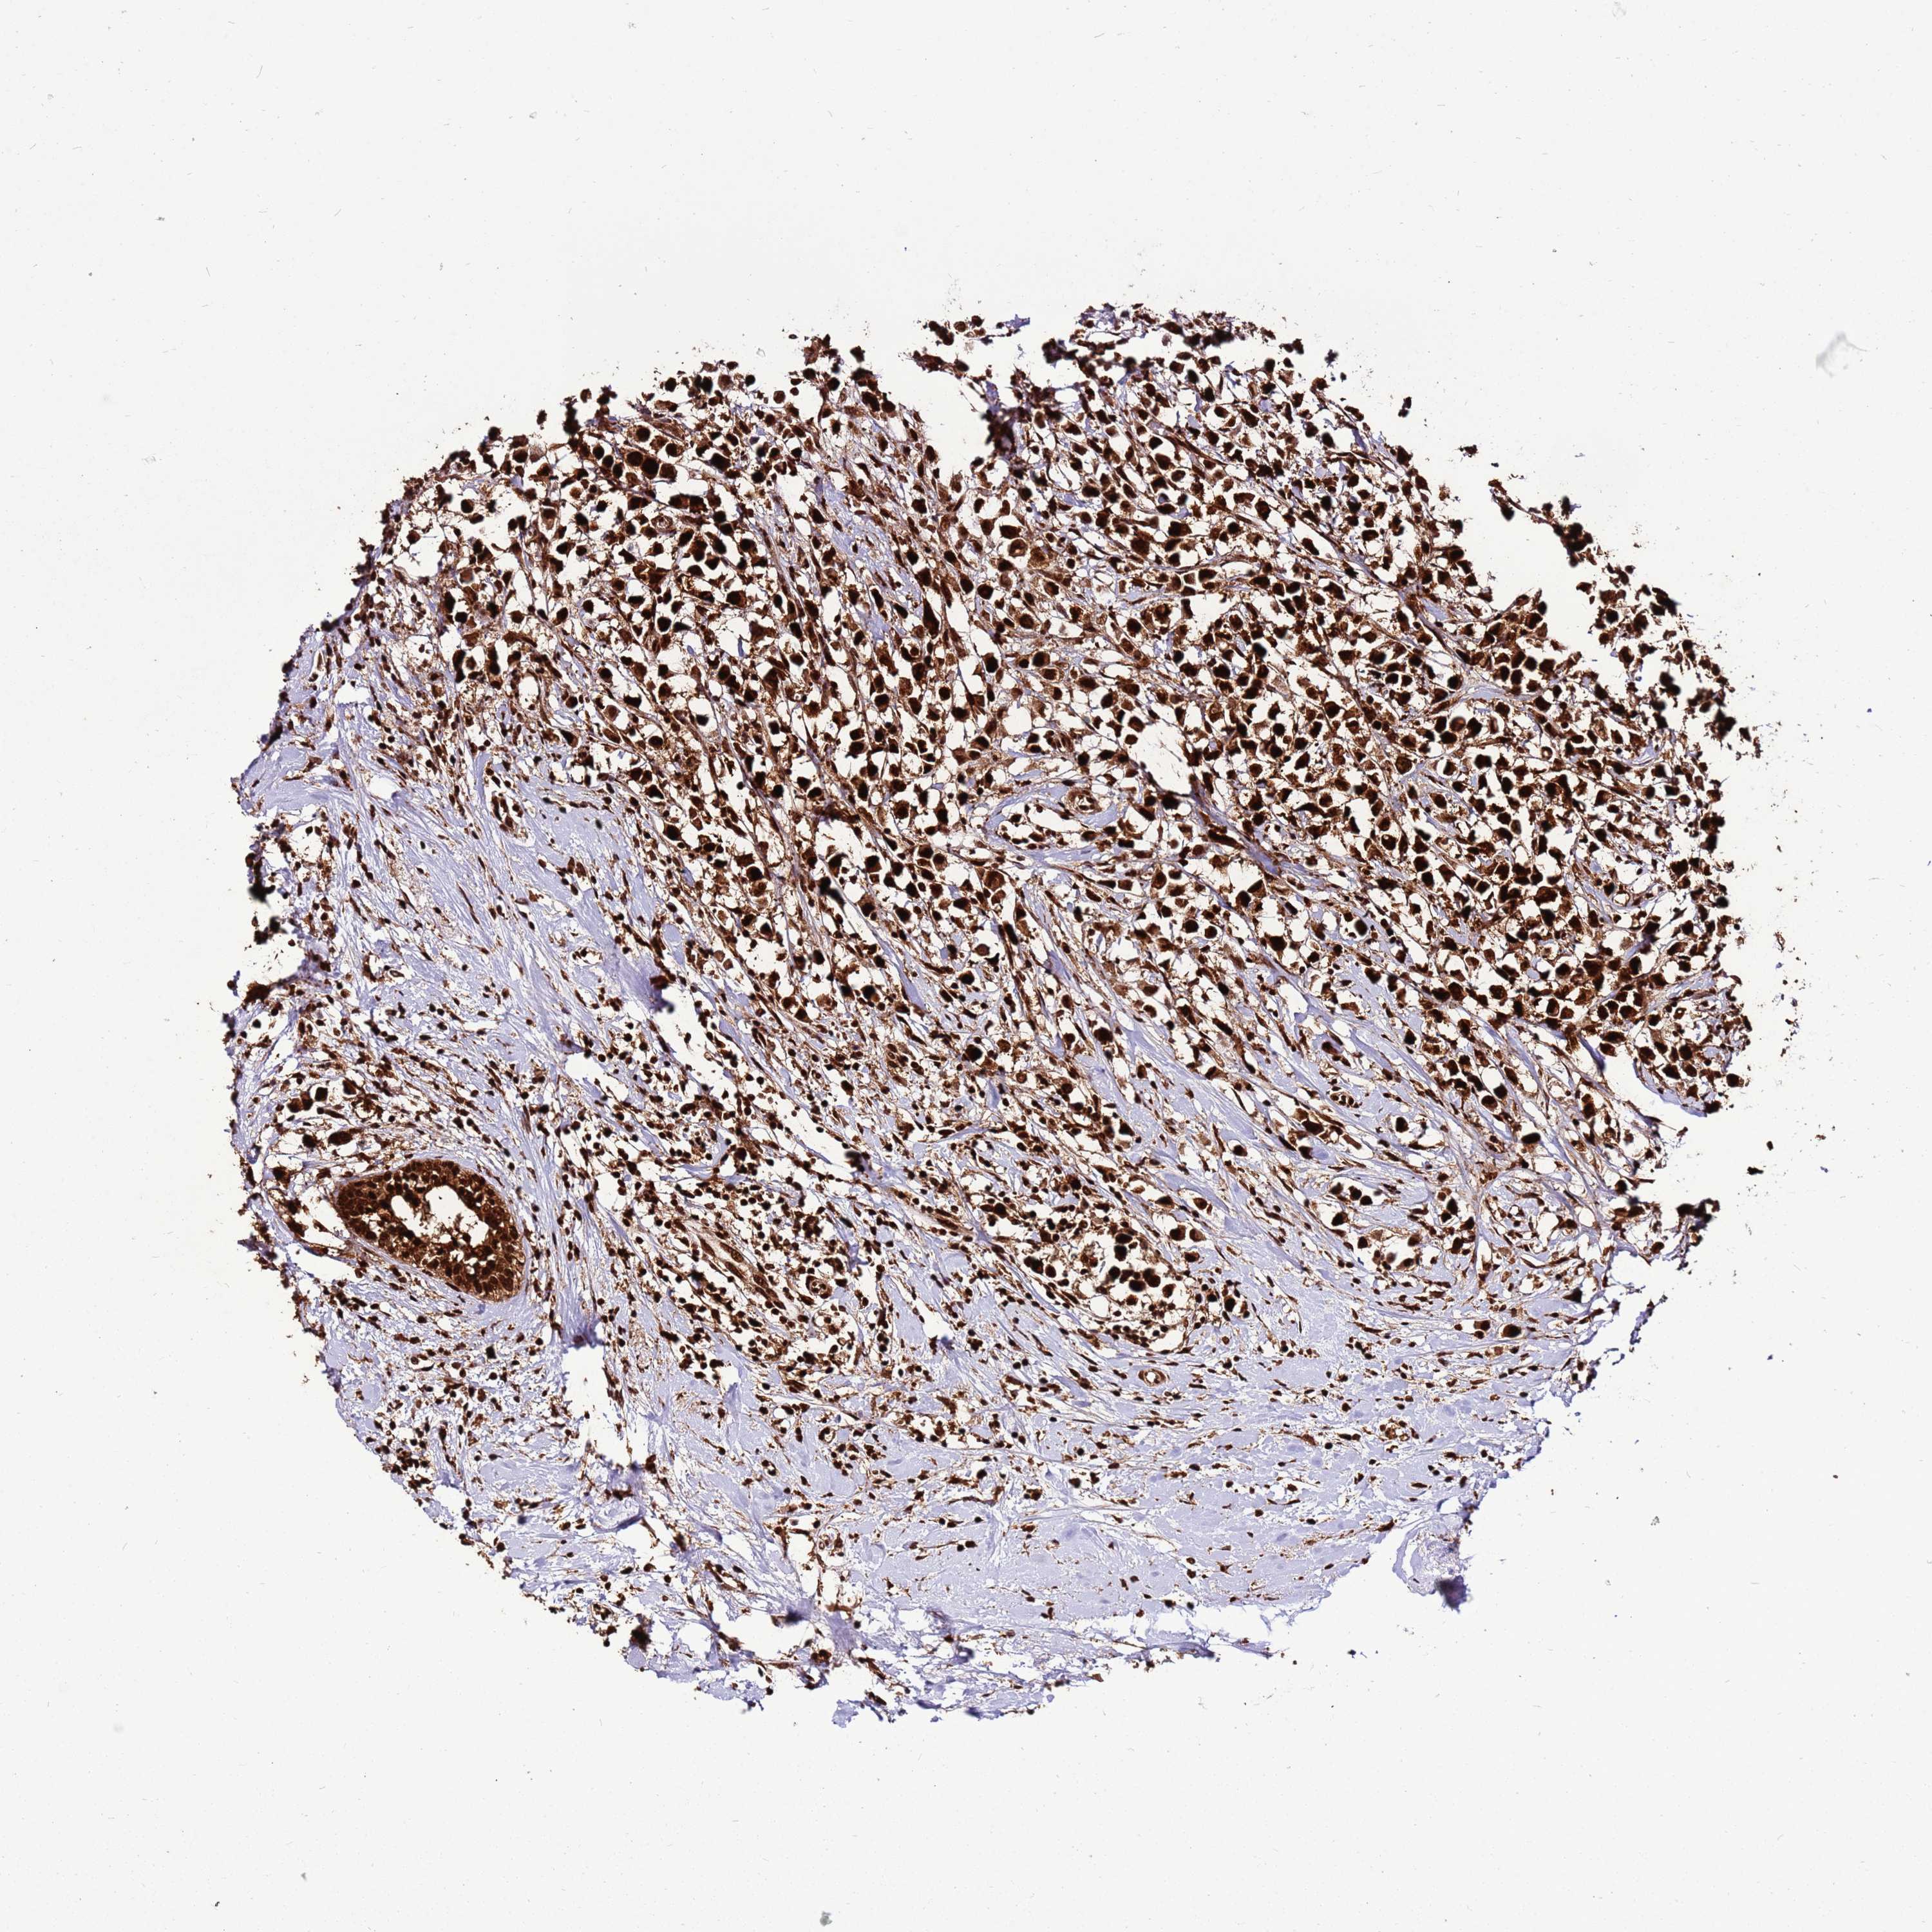

CANCER BREAST CANCER Show tissue menu

BRCA TCGA BRCA VALIDATION PROTEIN EXPRESSION